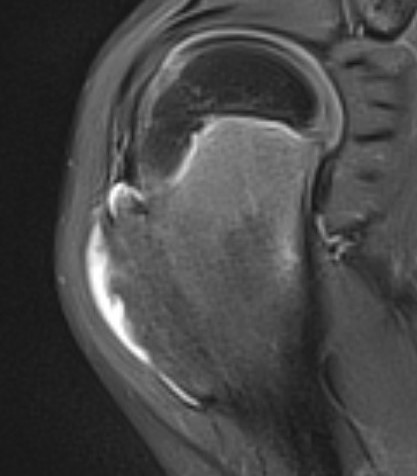

MRI

Cartilage cap iso-intense with hyaline cartilage